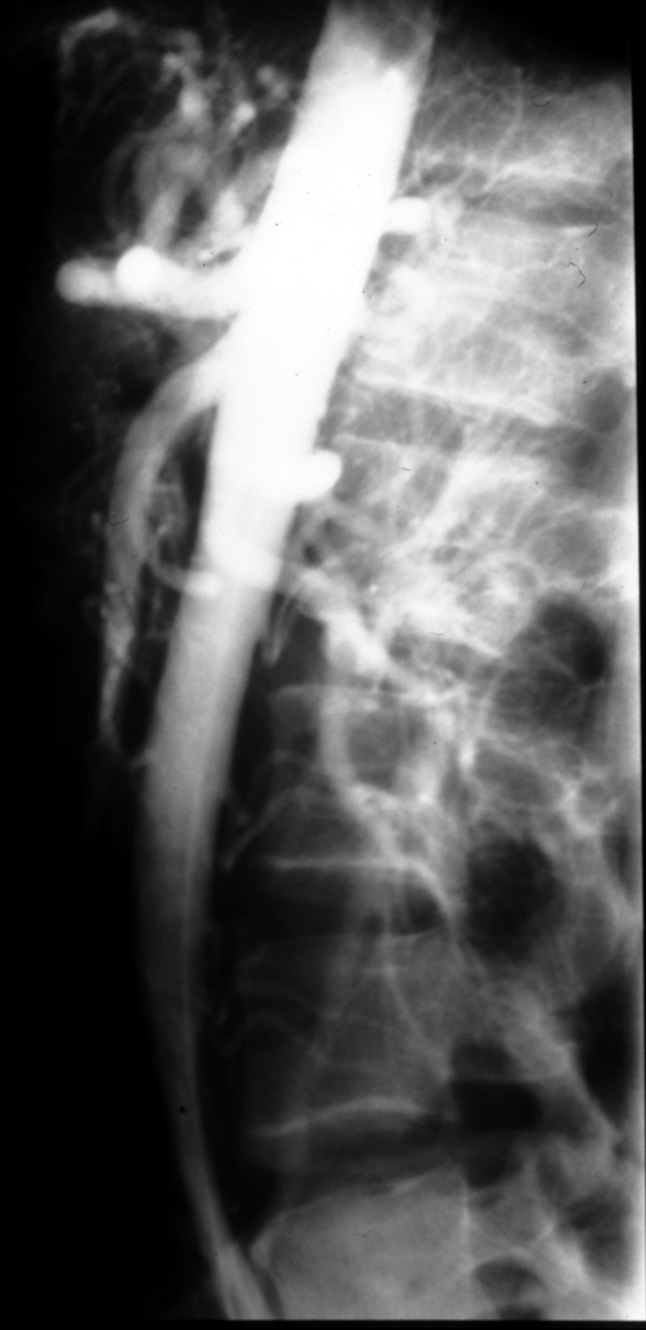

MS I 119 (Lateral) - Normal Aortogram - Lateral

Identify: celiac axis, SMA